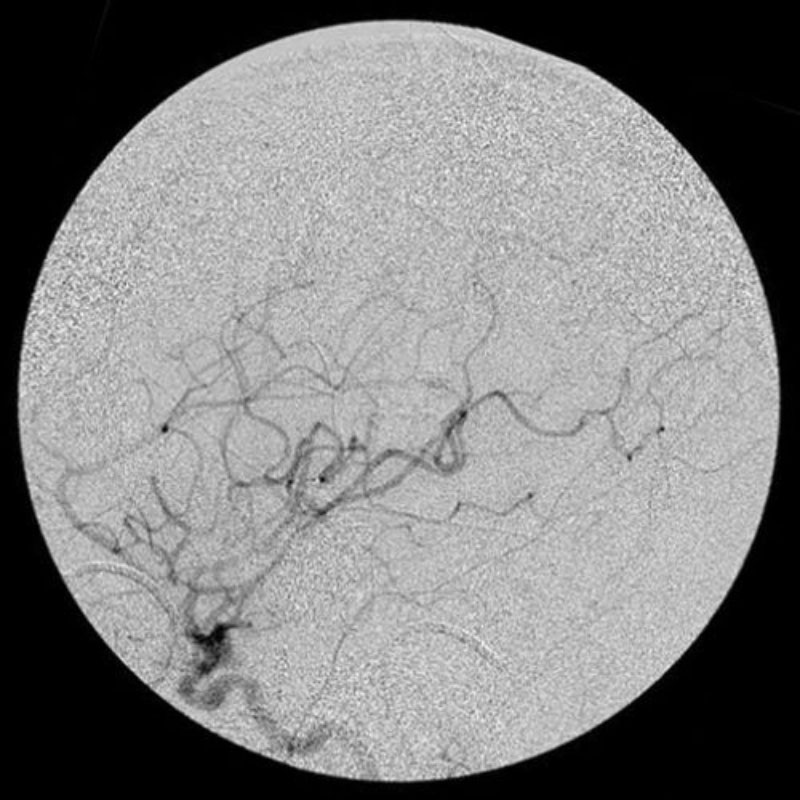

'19年5月

30代

富永/久貝

右中小脳脚 出血再発

SM 3(S1,E1,V1)

米国の病院

No.359 モニタリング

No.359 手術前

No.359 手術中

No.359 手術後

出血既往があり。2回の手術前血管内手術の後に、

Lateral transpeduncular approachにより再々出血予防を目的に

摘出手術を行う。完全摘出であることを確認した。

手術による合併症や後遺症なしで退院した。経過良好。